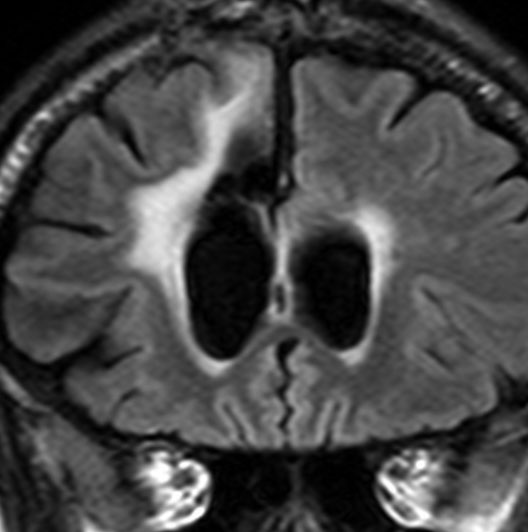

全脳照射後の脳内石灰化(青年期例)

1985年,17才のときに松果体ジャーミノーマで全脳照射45グレイ,18分割,1回2.5グレイの放射線治療を受けました。照射後の数年は普通に社会復帰ができていたということで,大学を卒業し,就職もしていました。しかし,20代後半くらいから認知機能低下(高次脳機能障害)が目立つようになりました。41才で脳幹部梗塞になりましたが,放射線治療が原因の脳血管障害でした。大脳にも小脳にも広範囲に脳内石灰化が散らばっています(白い点状に見えるもの全て)。30代からさらに進行悪化しました。脳の萎縮は目立ちませんが,MRIでは,大脳基底核の多数のラクナ梗塞,多数の海綿状血管腫,中大脳動脈の壁不整と狭窄もみられました。45才で介護施設に入所しています。このような所見は,1日線量2.5グレイを用いていた頃の小児患者さんでみられます。